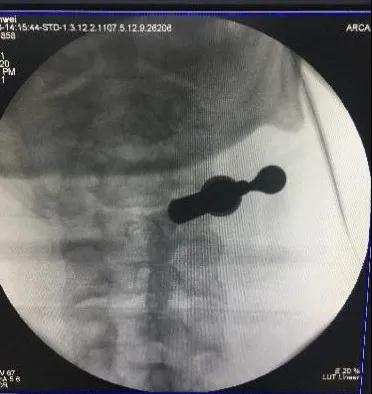

术前脊髓造影后颈椎CT。

颈椎间盘突出明显。